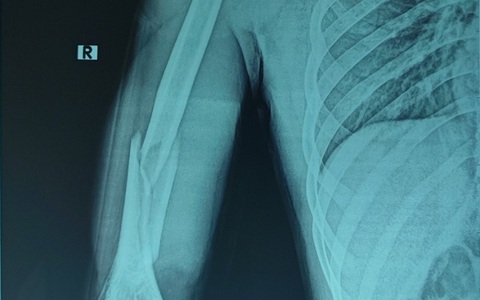

Đang chơi pickleball, một người mẫu (30 tuổi) bị gãy 1/3 giữa thân xương đùi bên trái. Việc mổ cho bệnh nhân gặp khó khăn vì bệnh nhân có chiều cao 1,78m, đường gãy xương tét dọc xuống theo xương đùi trái.

Sau khi chơi vật tay cùng bạn, nam thanh niên 21 tuổi nhập viện trong tình trạng cánh tay sưng đau, biến dạng, hạn chế vận động.